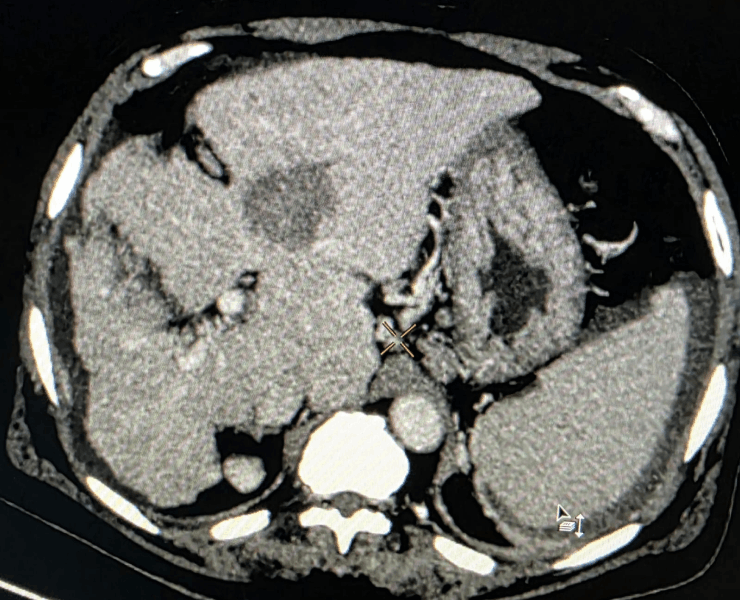

Microwave ablation of liver cancers

Liver tumor

- Thermal ablation (radiofrequency or microwave): destroys tumour tissue by heating it from within through a thin needle placed under USG/CT guidance.